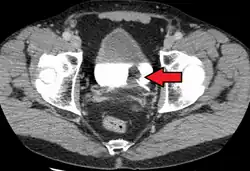

| Transitional cell carcinoma of the bladder. The white in the bladder is contrast. | |